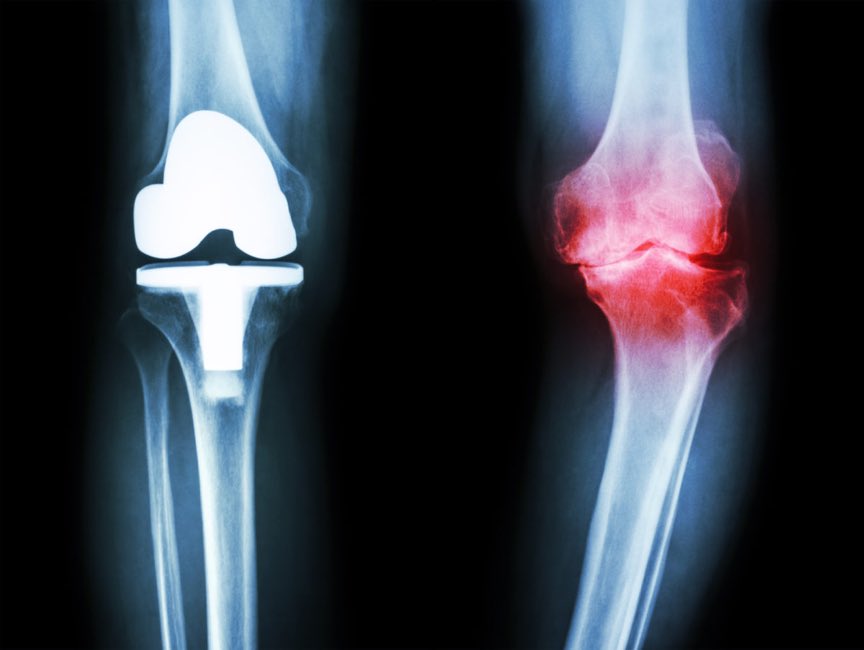

وفي حال عدم تحسن الأعراض يكون الخيار الجراحي هو الأنسب والافضل لمساعدة المريض بتحسين الأعرض والإستمتاع بحياته اليومية

بعمليات تلبيس او استبدال مفصل الركبة